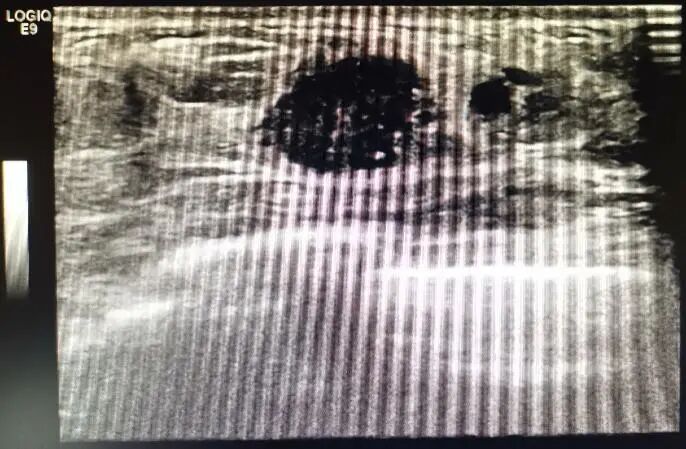

彩超:左乳中央腺体层可见大小约4.10×1.80cm的低回声团块,边界不清,边缘毛糙,其内回声分布不均匀,CDFI示血流信号Ⅲ级。双侧腋窝及双侧锁骨上下未见明显肿大的淋巴结。

彩超提示:1. 左乳外上及内上低回声团块,BI-RADS-US 4a类;